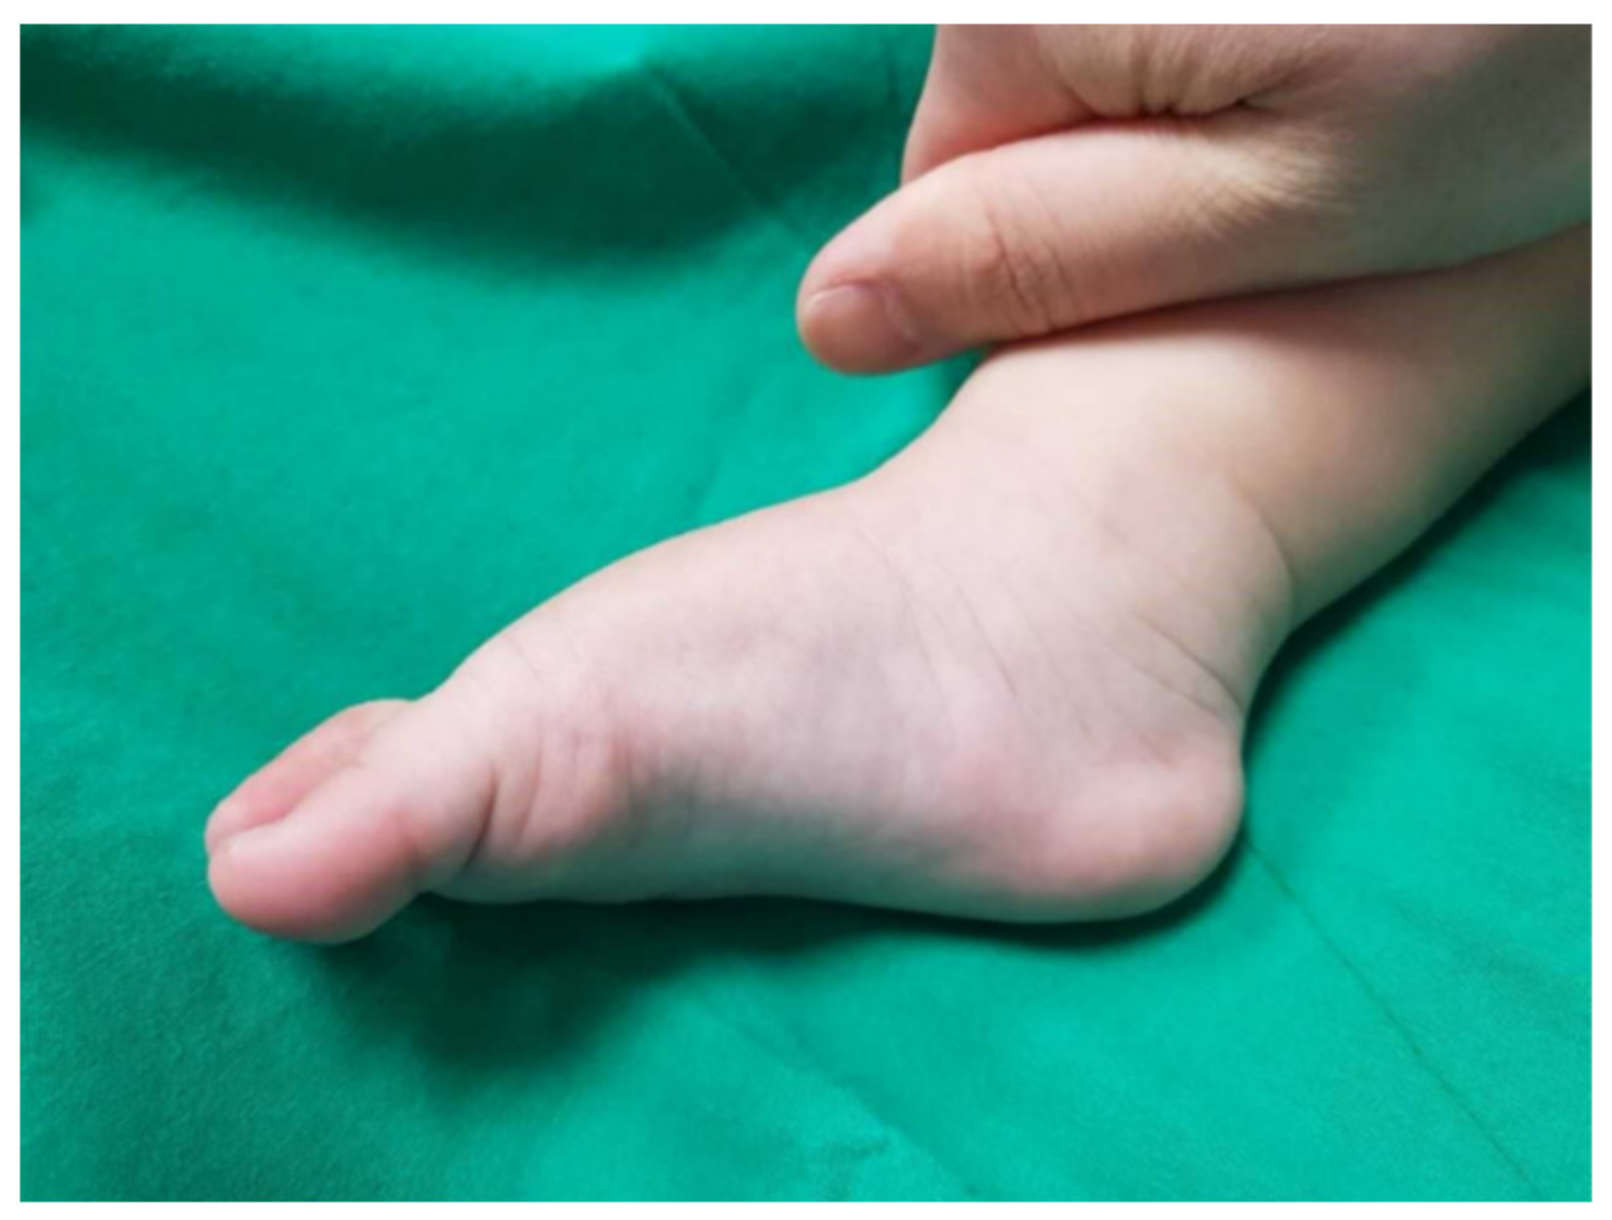

| 1 | F | Right | 5 | forefoot pronation, cavus, equinus | 3 | posterior | 4 | 173 |